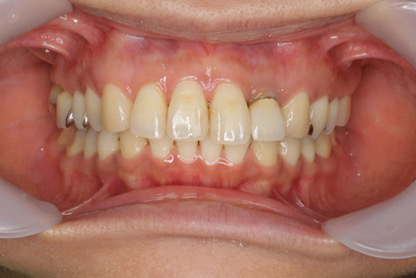

■症例1

Before

After